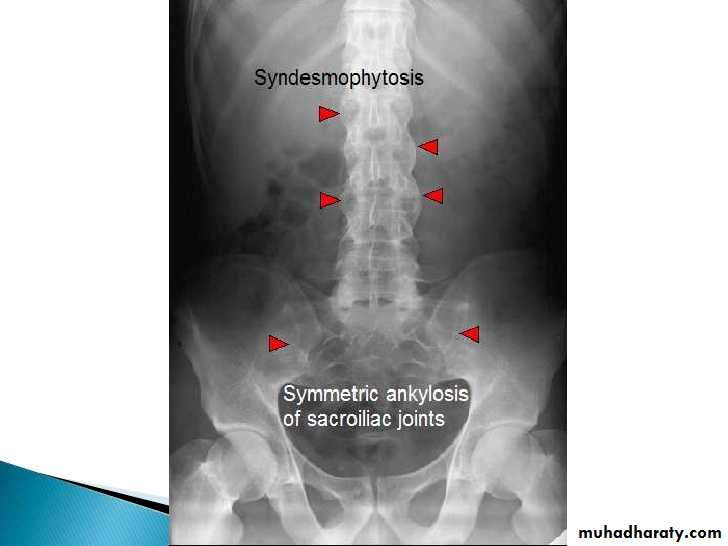

Spine

• Early changes include squaring of the anterior vertebral body

• Progressive mineralization of Sharpey’s fibres to form osseous bridging syndesmophytes

• Bamboo spine

• Dagger sign apperance

Ankylosing Spondylitis

Erosions and sclerosis on iliac side

Bamboo spine